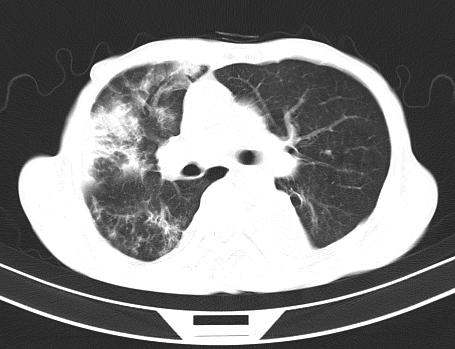

以下是引用gaoshengjiang在2008-5-30 19:53:00的发言:[br]右上叶可见大片实变影,其内可见充气支气管影及囊状影,右上叶尖端支气管走形区可见结节样影,左侧胸腔内可见胸腔胃影。纵隔淋巴结肿大。[br]考虑:1.右上肺阻塞性肺炎伴肺脓肿形成。支持转移所致。[br] 2.左侧胸腔胃。